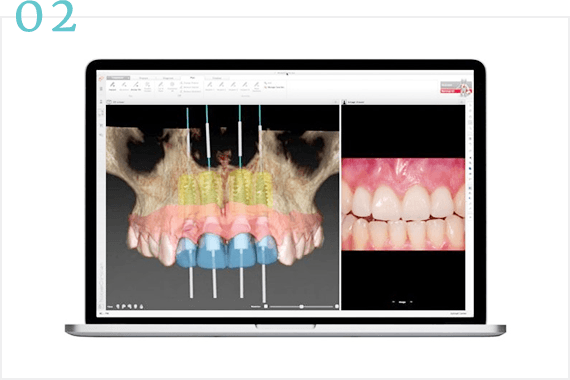

CASE 02

治療内容

ここにテキストが入ります

ここにテキストが入ります。ここにテキストが入ります。ここにテキストが入ります。ここにテキストが入ります。ここにテキストが入ります。ここにテキストが入ります。ここにテキストが入ります。ここにテキストが入ります。ここにテキストが入ります。ここにテキストが入ります。